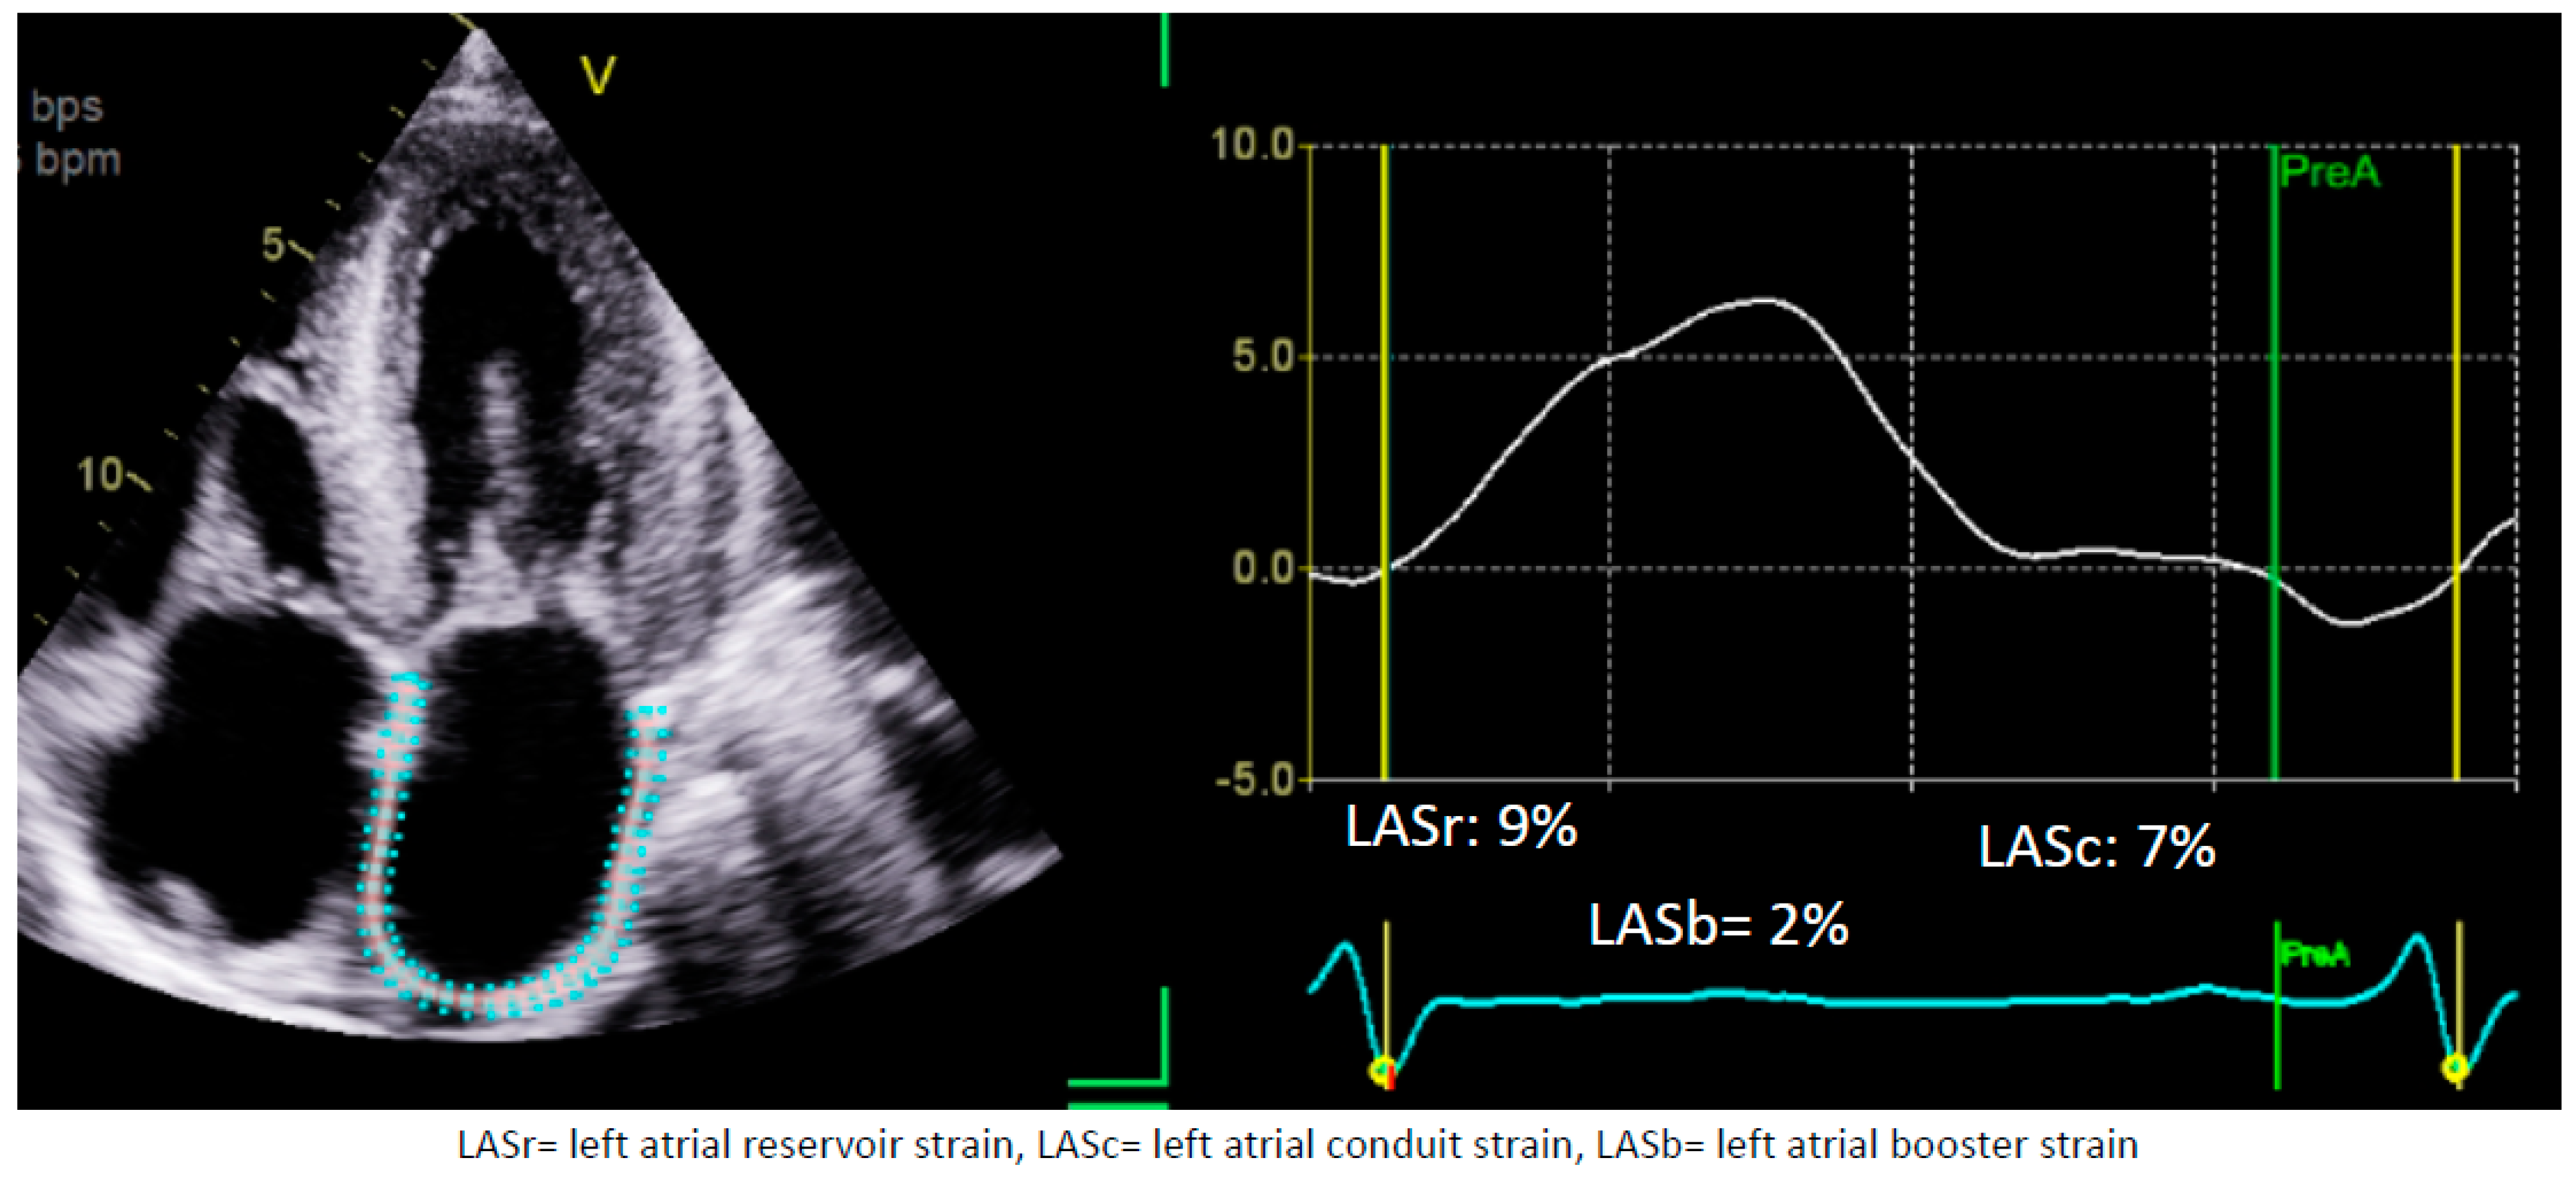

1.1. Assessment of LA Strain